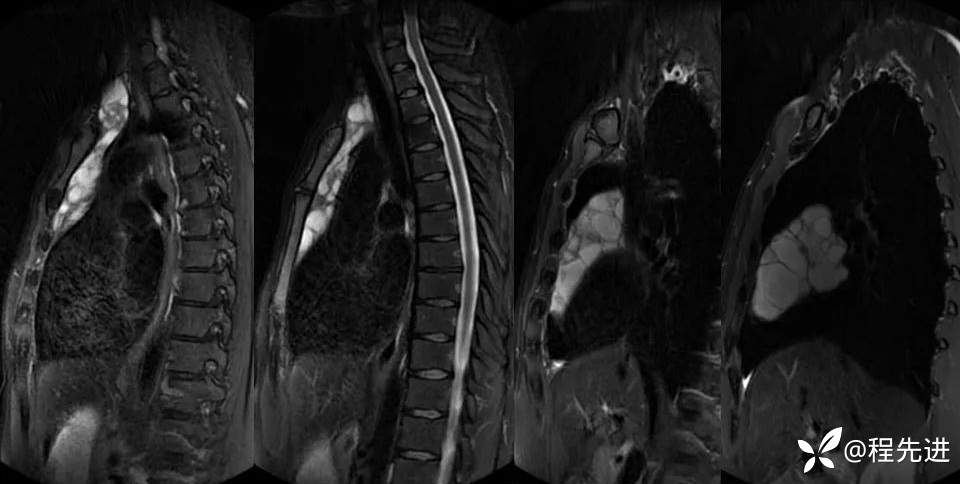

DWI

同反相位